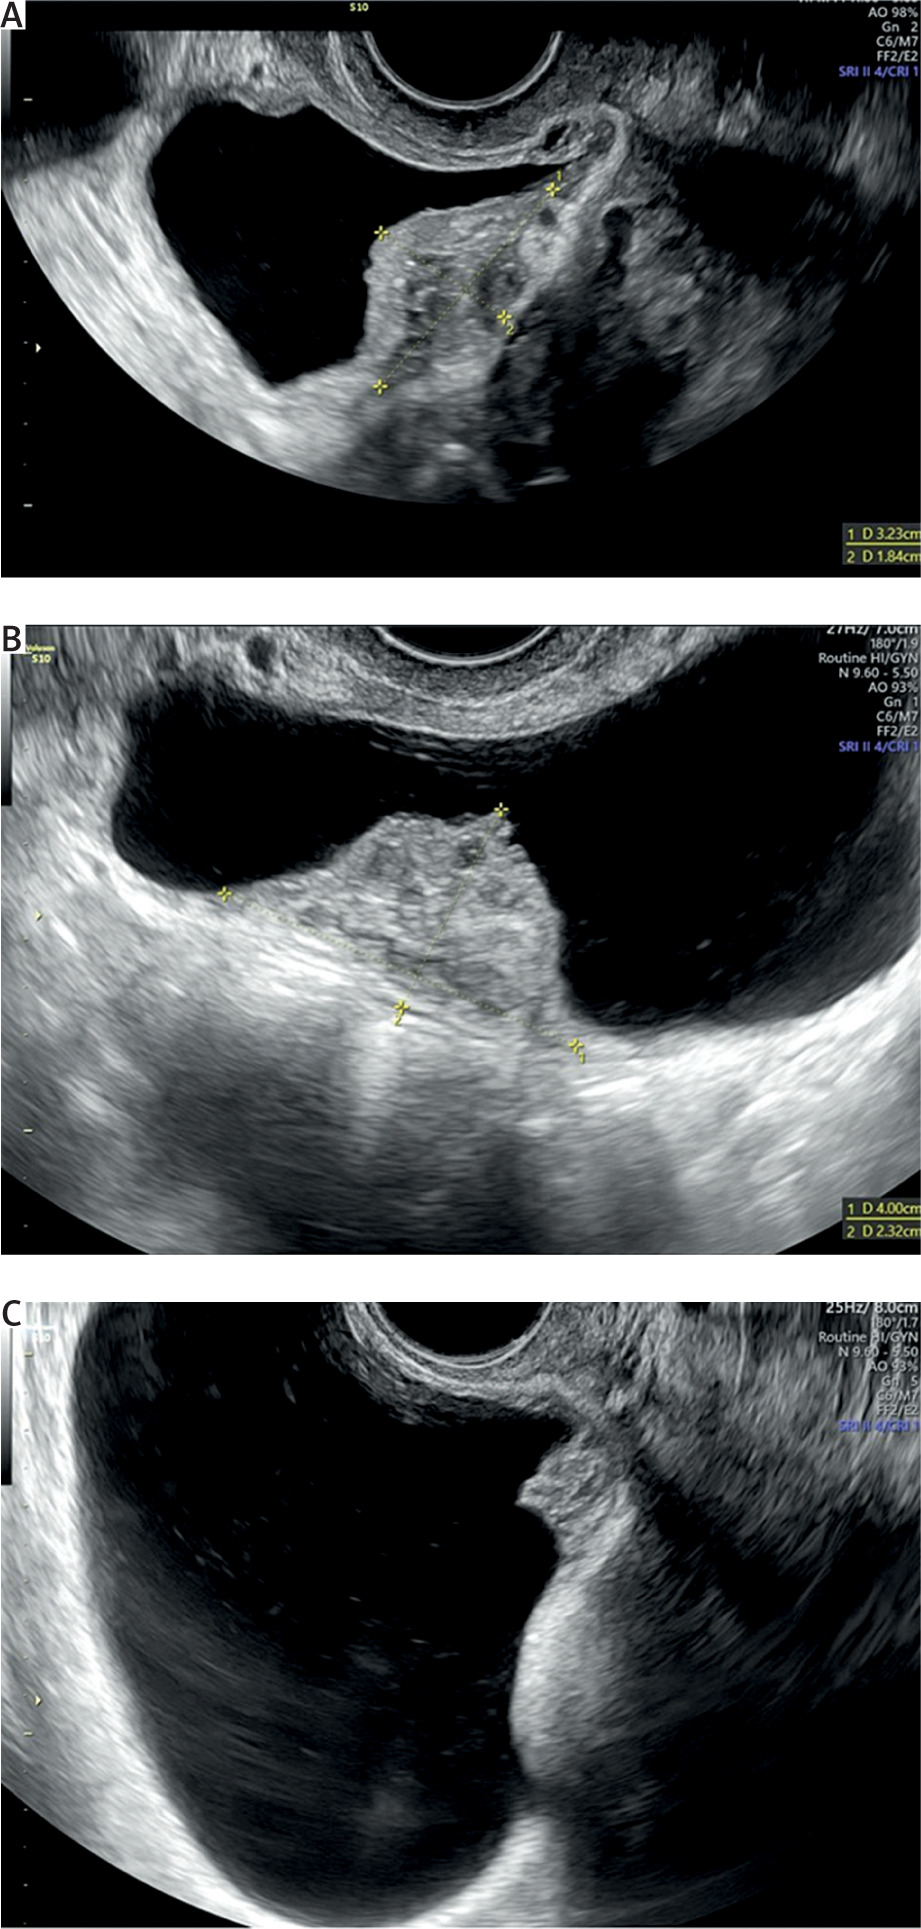

Endometriosis is a common gynaecological disease, which affects 10–15% of women in reproductive age. It is defined as the presence of functional endometrial foci outside the uterine cavity. Patients can experience a variety of nonspecific symptoms, but the most common are pain and infertility. Apart from this, endometriosis may present with haematuria, fatigue, painful rectal bleeding and metabolic and psychiatric disorders such as hypoglycaemia, depression, or anxiety [1–3]. Female infertility can be caused by different mechanisms such as fallopian tube destruction, chronic pelvic inflammation, changes in the immune system functions, and altered hormonal balance. Furthermore, inflammatory cytokines and cells affect eutopic endometrium, causing an implantation failure [1, 4]. Endometriosis is divided into three types: ovarian endometriosis, superficial (peritoneal) endometriosis, and deep endometriosis (DE) [1]. Deep endometriosis is defined as endometriosis invading pelvic organs more than 5 mm beneath their surface. One of the rare forms of endometriosis is urinary tract endometriosis (UTE), which can either occur as deep or superficial endometriosis. Urinary tract endometriosis affects 0.3–12% of women with endometriosis and this condition refers to/occurs in 20–52.6% of patients with DE [3, 5]. The most common location of UTE is the bladder, while the most dangerous type of UTE is ureteral endometriosis, because it can lead to silent and irreversible kidney damage. Bladder endometriosis (BE) is defined as the presence of endometrial foci in the vesical detrusor muscle (Figure 1). Bladder endometriosis most commonly affects the base and dome of the bladder [3]. The vesicouterine pouch or anterior cul-de-sac is also a common site of endometriotic involvement. Either peritoneal or deep endometriotic implants involving the serosal surface of the uterus often determine adhesions between the peritoneal folds of the bladder dome and the uterus with anteflexion of the uterus and obliteration of the anterior cul-de-sac. Bladder endometriosis was described for the first time in 1921 by Judd [6]. Since then, numerous case reports and research studies have been published regarding this topic. Despite the wide literature, the pathogenesis of BE is still unclear. Most popular theories explaining the pathogenesis of BE are retrograde menstruation, coelomic metaplasia, and the spread of stem/progenitor cells [3, 7]. At the moment, retrograde menstruation theory is considered to be the most explanatory. This theory states that menstruation blood with functional endometrial cells flows to the pelvic cavity through the fallopian tube orifices [1, 8]. Endometrial cells adhere to the peritoneum and start the inflammation facilitating the vesicouterine pouch endometriosis (EVUP) development and bladder infiltration. Novellas et al. have found that the endometrial cells implant to the outer layers of the bladder and later infiltrate the inner layers [9]. On the other hand, the retrograde menstruation hypothesis cannot explain the isolated BE form, in which case other theories seem to be more suitable. In addition, BE may be of iatrogenic origin, such as a consequence of bladder destruction during caesarean section (CS) [3, 7]. Bladder endometriosis presents a range of nonspecific symptoms such as urinary bladder pain, cyclic or noncyclic pelvic pain, dysuria, dyspareunia, increased urinary frequency, urinary incontinence, haematuria, and elevated intravesical pressure. Thus, the differential diagnosis of BE is challenging considering various mimicking diseases such as urinary tract infections, interstitial cystitis, bladder stones, and carcinoma [3, 7, 10]. As a chronic inflammatory disease, endometriosis can also have an impact on mental health, sleep quality, and life quality in general. The sleep and life quality of patients suffering from endometriosis is poorer than in healthy women. The main cause of sleep disturbances is pain and nocturia, but some researchers indicate that sleep insufficiency can in turn increase inflammation processes and worsen the pain. A similar pathophysiological mechanism can cause psychiatric disorders [11]. The most frequently used imaging modality in BE and EVUP is transvaginal ultrasonography (TVS) (Figure 2). Besides TVS, magnetic resonance imaging (MRI), transabdominal ultrasonography (US), or cystourethroscopy are used as supplementary imaging methods for those conditions [3, 10]. Surgical resection of endometrial foci is a gold standard therapy, which enables/makes it possible to completely treat the disease [3, 7, 12]. Surgical removal may be done by laparotomy, laparoscopy, or using a surgical robot. Apart from surgical resection, pharmacotherapy plays a key role in BE, leading to clinical improvement [3, 7]. Several treatment options such as progesterone-based therapy, combined oral contraception, and GnRH analogues are available. In our study we have decided to analyse the variety of symptoms and the outcomes of laparoscopic surgery done on BE and EVUP patients.

Numerous analyses of DE imaging methods are available in the literature. Guerriero et al. performed a systematic review with patients who underwent TVS before surgery, showing sensitivity of 62% and specificity of 100% for this diagnostic method [20]. Transvaginal ultrasonography is a reliable first-line imaging modality for the diagnosis of endometriosis involving uterosacral ligaments, rectovaginal septum, vagina, and bladder, particularly in patients with controlled pain and absence of intestinal stenosis or ureteral involvement [21]. Transvaginal ultrasonography can also be used for the follow-up of patients with ultrasonographic diagnosis of DE, whose symptoms have subsided during the medical treatment, or for those trying to become pregnant [20]. Holland et al. proved that the location of endometriosis lesions affect the diagnostic accuracy of TVS, obtaining the sensitivity and specificity of 100% for patients with BE, and only 16.7% sensitivity for patients with EVUP (specificity remained at 100%) [17]. High accuracy of the US in diagnosing BE was also shown in several other studies [22, 23]. In order to assess the extent of the endometriosis lesions in more detail, MRI can be chosen as a supplementary imaging modality. It is characterized by high accuracy for detecting endometriosis lesions and particularly foci hidden beneath healthy tissue or obliterated Douglas pouch [24].